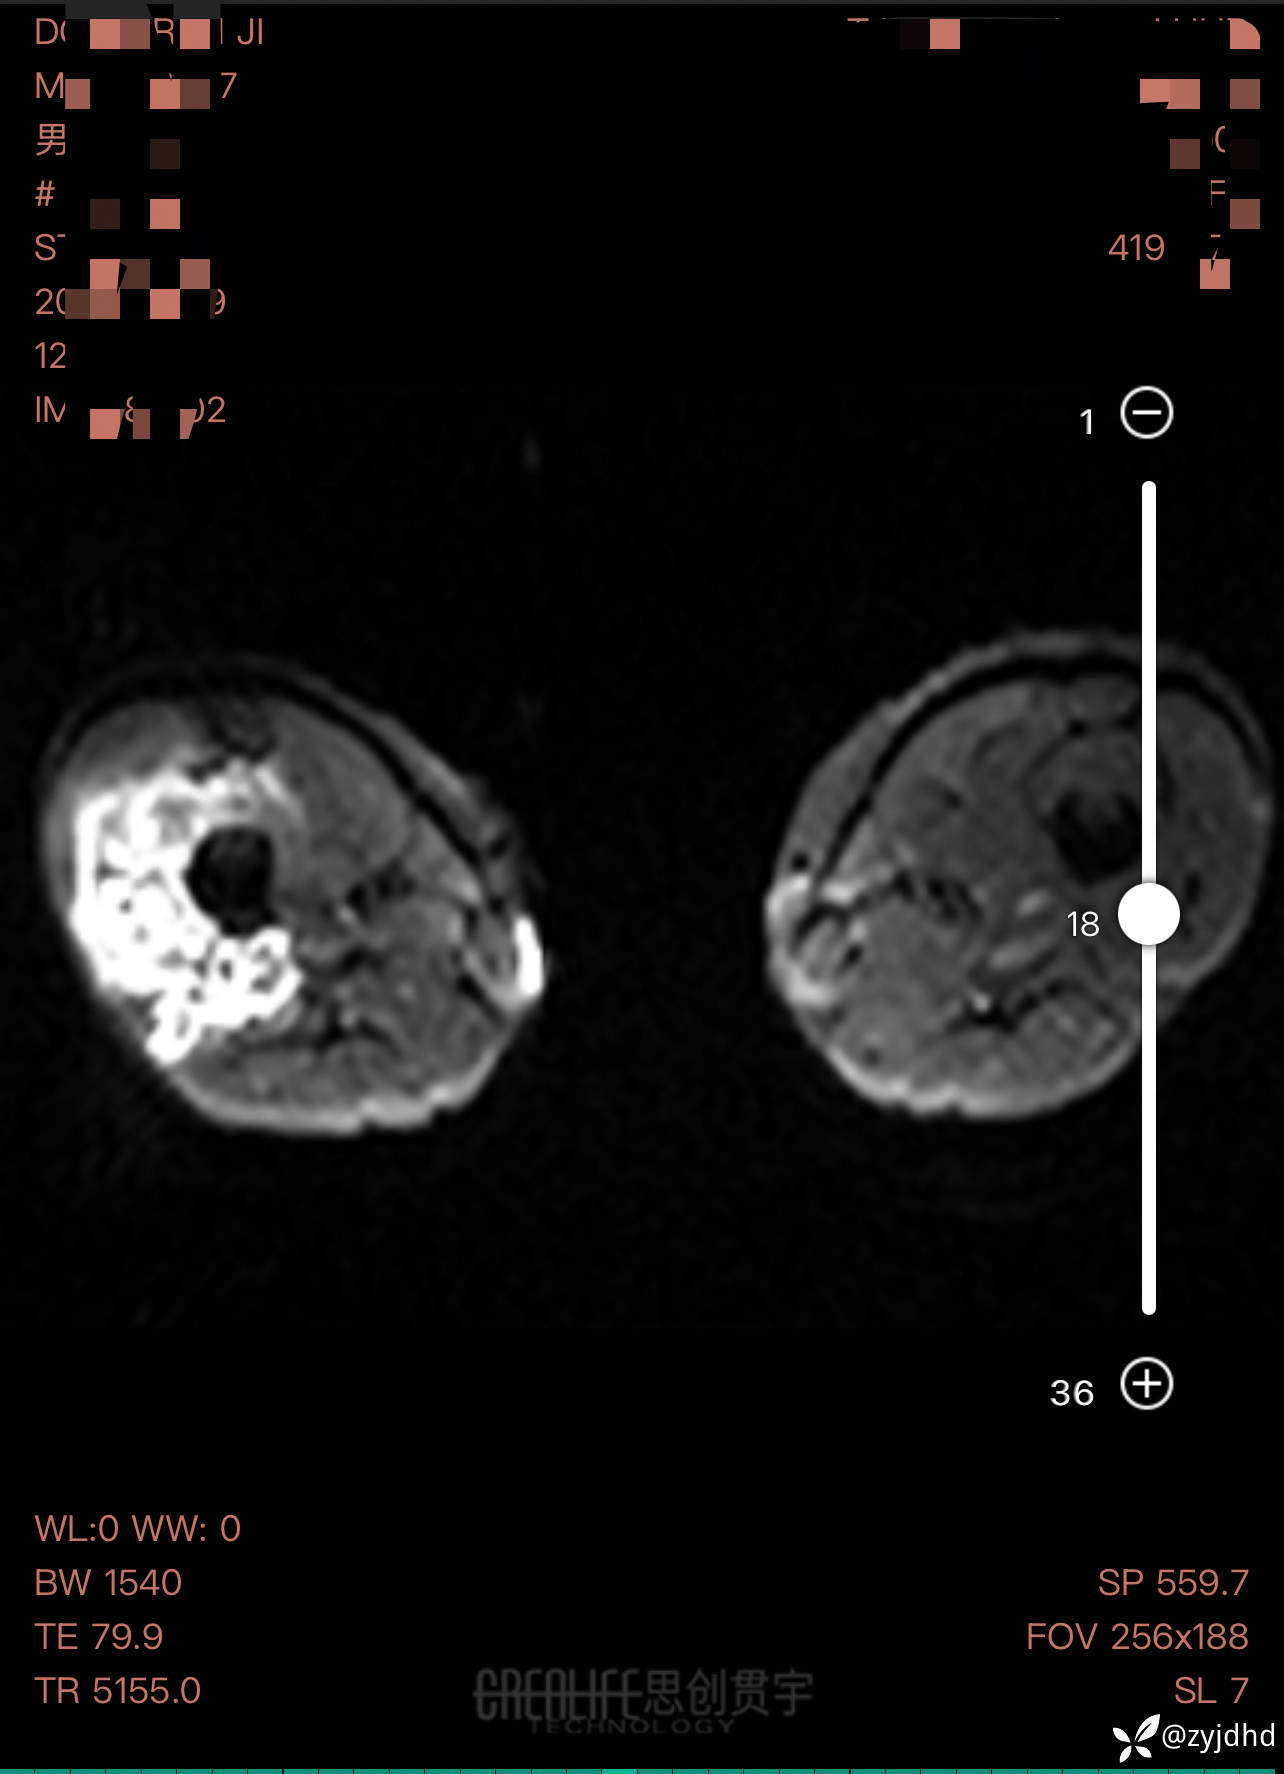

男性,发现右大腿肿物20年。